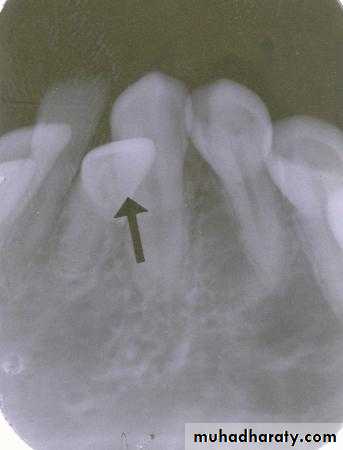

canine film

premolar filmIs the radiopaque object identified by the arrows located on the buccal or the lingual?

Lingual. The tube head moves mesially from the premolar film to the canine film. The object also moves mesially, starting out distal to the first molar on the premolar film and ending up mesial to the first molar on the canine film. This object represents the tip of the palatal root of the second molar and is located distal to the first molar and in a lingual relationship

root tip